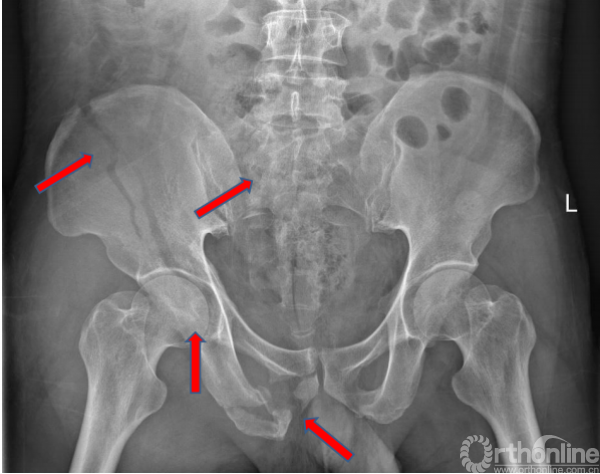

术前X线(2017.09.17)

骨盆正位、骨盆入口位、骨盆出口位